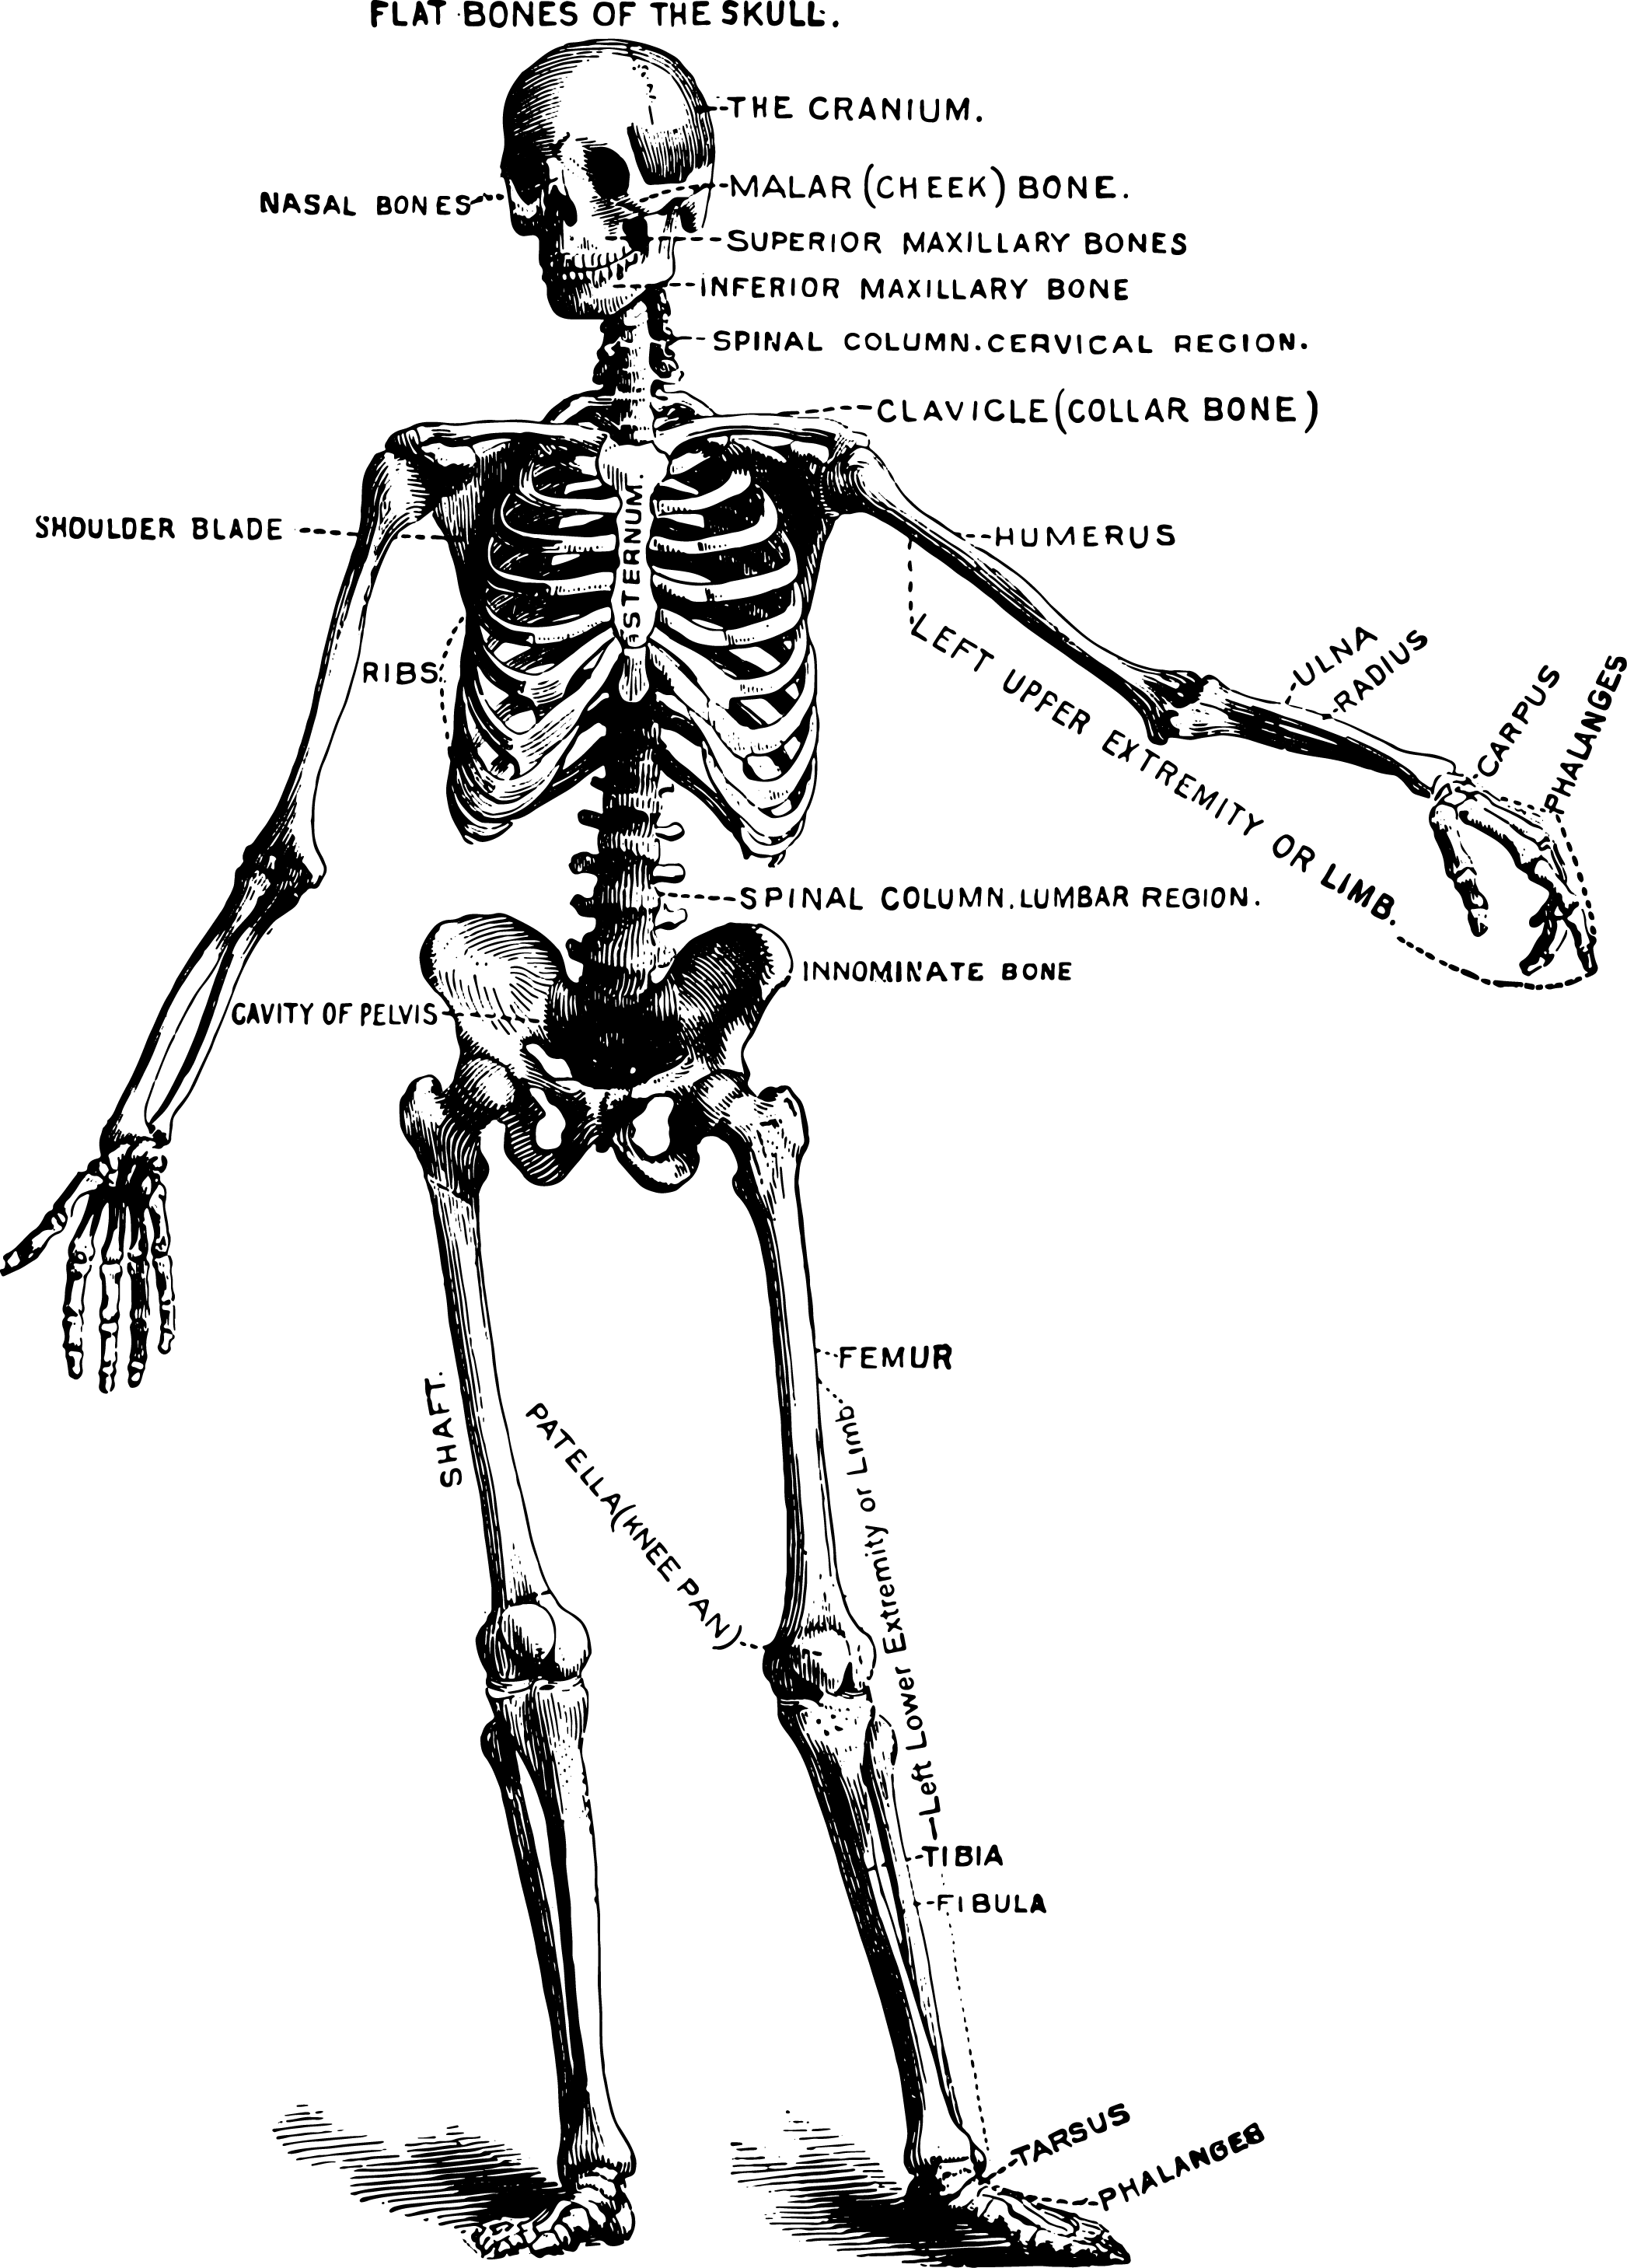

Kiropraktor

Kjeveteamets kiropraktor vil snakke med deg om din egen opplevelse av plagene, samt utføre ortopediske og nevrologiske tester i tillegg til å vurdere muskulatur i nakke og kjeve for å stille riktig diagnose, og for å utelukke alvorlig sykdom. Muskelspenninger, slappe leddbånd, og redusert bevegelighet i kjevens og nakkens ledd er svært vanlige årsaker til TMD. Uvaner, overbelastning, stress og uheldig ergonomi på jobb, hjemme og i sosiale situasjoner er også kjente bidragsytere.